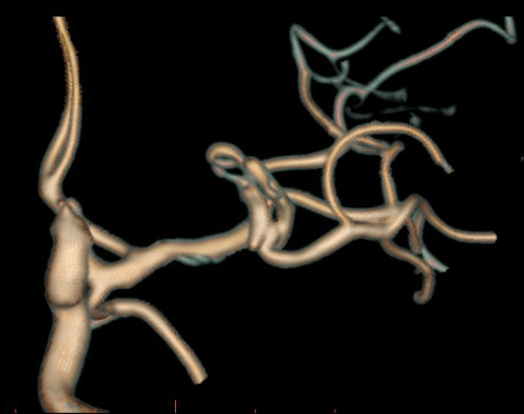

Clipping di aneurisma complesso M1-M2 di sinistra – ricostruzione biforcazione arteria cerebrale media

Aneurisma Biforcazione ACM – Vito Fiorenza